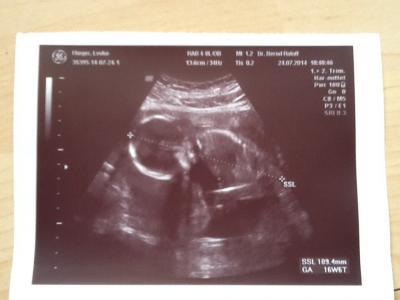

Hatte auch heute meinen monatliches FA-Termin..... Und es war fantastisch. Unser Baby ist 11cm groß und hat sich ordentlich bewegt. Leider auch noch kein Outing weil das Baby mit dem Rücken zu uns lag. Ach ich bin ganz entzückt;-) Jetzt muss nur noch der Bauch wachsen...der lässt sich nämlich noch Zeit. War gestern das erste mal beim Yoga. Ich kam mir sooooooo unschwanger vor mit meinen 17ssw zwischen den ganzen 25-33 ssw Schwangerin. Naja ansonst war es ganz witzig. Ist bestimmt ganz hilfreich für die Geburt. Liebste Grüße

Bild zu Ich auch - Forum für Januar - Mamis